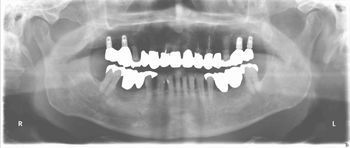

下顎fullインプラント

下顎のフルインプラントです。6本のインプラント(4本では不安です)を埋入して上部構造はスクリュウで固定してます。下の総義歯はみなさんどうしても浮き上がってきて食べにくいです。インプラントを埋入して即時負荷をかけるのはどうかと思いますが、骨と結合した後ならかなり頑丈な上部構造ができて、硬いものでも噛みやすくなります。

●● 様 男性 70代

治療の期間・回数:6か月、10回

治療の価格:150万円/下顎

治療のリスクや副作用:手術後に、痛みや腫れ、出血、合併症などを引き起こす可能性があります。噛む感覚がご自身の歯と異なる場合があります見た目がご自身の歯と異なる場合があります。手術後にメインテナンスを継続しないと抜け落ちる可能性があります。